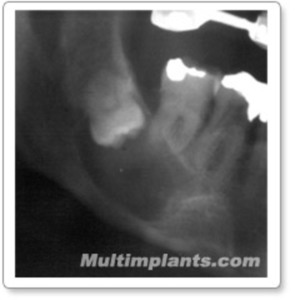

Another clinical case. We can see multiple retained teeth in the same patient.